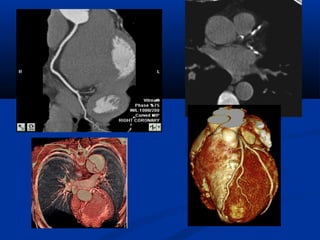

U maùu vuønghaømU maùu vuøng haøm (T)/(T)/ Daõn tónh maïchDaõn tónh maïch caûnh ngoaøi (T)caûnh ngoaøi (T)

Xaùc ñònh vò tríxöông söôøn treân CT

NOÄI SOI AÛOPHEÁ QUAÛN